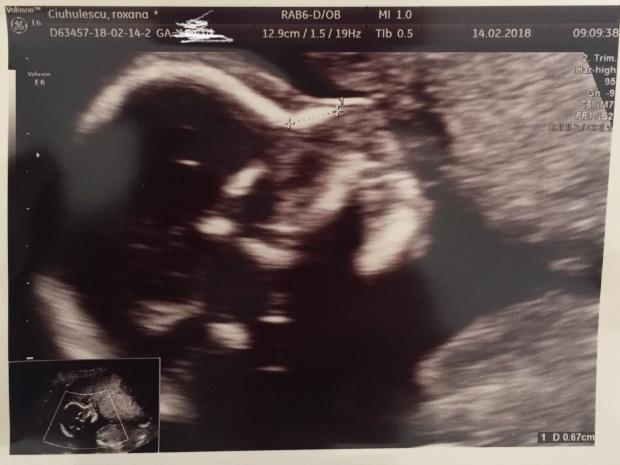

Foto: Roxana Ciuhulescu

Prezentatoarea a publicat şi ecografia, precizând că va avea un băieţel, dar şi că anul acesta va face nunta: „Cu toţii suntem extrem de fericiţi şi ne dorim ca acest copil să se nască sănătos. Aşa că acest an ne vom bucura de un dublu eveniment: căsătorie & botez“.